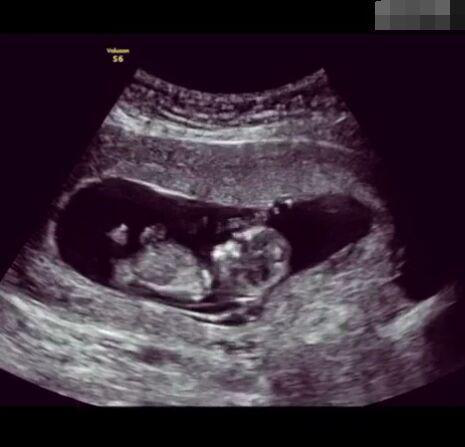

圖片8.png

那些做了B超檢查確定胎兒男女,生下來后發(fā)現(xiàn)不對的,多半是因為在B超檢查時寶寶太調皮,以致影響了檢查準確性。就比如說,有的女寶寶在媽媽肚子里玩自己的臍帶,把臍帶夾到了兩腿中間,B超就有一定幾率拍出來好像是男寶寶的特征,導致被誤認為是男孩子。還有些男寶寶過分害羞,在做B超時雙腿緊緊并攏,醫(yī)生也很難判斷男女,只好大致猜測是女孩,就又造成了誤會。因此,B超亦不是萬能的。